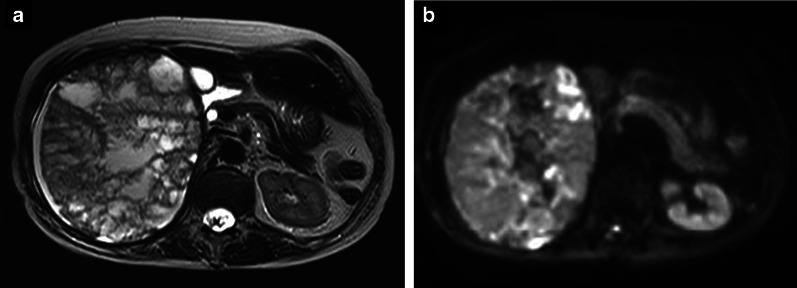

Fig. 3.

MRI. a T2-weighted imaging. The inside of the tumor showed a mosaic pattern with a mixture of high and low signals. b Diffusion weighted imaging: b = 1000. A high signal was observed predominantly at the tumor margin